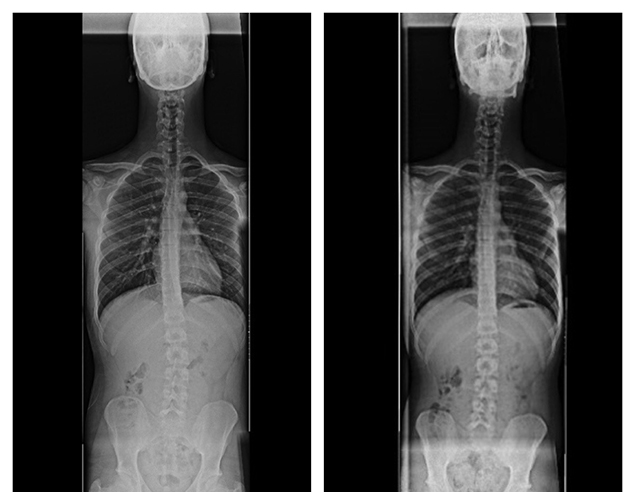

Gerçekten de 7-8 derecelik bir skolyozum olduğu ortaya çıktı. Bunu duyunca çok moralim bozuldu, hedefimin önünde böyle bir engel olmasını kabullenmedim. Bu rahatsızlığı nasıl yenebileceğimi araştırırken, egzersiz yapmam gerektiğini öğrendim. Çevremizdeki pek çok kişiden, fizyoterapist Elif Akıncı’nın bu konuda iyi olduğunu duyunca, kendisinden randevu aldık. İlk görüşmede yaptığı kontroller sonrası, hemen egzersizlerimi planladı ve çalışmaya başladık. Elif Hanım, yaptığı kontrollerde skolyozun yanında belimde bir eğrilik olduğunu ve omuzlarımın öne doğru düştüğünü de söyledi. Zaten çektiği fotoğraflarda da belimdeki problem net olarak görülebiliyordu. Zaten sırtımda ve belimde çok ağrım vardı. Ağrıların sebebi, Elif Hanım sayesinde ortaya çıkmış oldu. Egzersizlere başlayalı 3 ay oldu. Şu an omuzlarım ve belimdeki eğrilik tamamen düzeldi, bel ağrılarımdan kurtuldum. Skolyozum için de yakın zamanda doktora gittim, çekilen röntgenlerde 3-4 dereceye kadar düştüğünü gördük.”